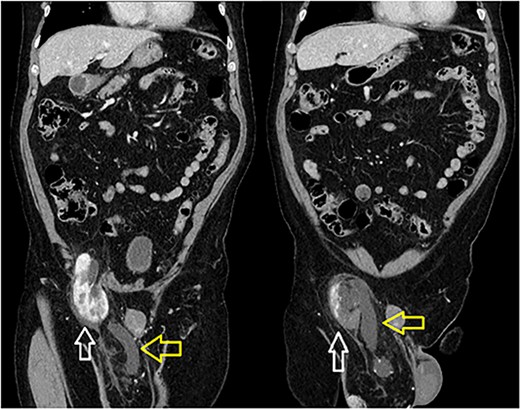

A 66-year-old Hispanic male presented to our emergency department with 1 week of right groin pain and swelling. He came to the hospital due to worsening pain. He denied any nausea, emesis or fever. He was passing gas and having bowel movements without difficulty. He denied any issues with voiding, hematuria or urinary urgency. His past medical history includes congenital deformity of his left upper extremity and past surgical history of open left inguinal hernia repair. His BMI is 32.5. His serum creatinine was 1.40 mg/dL. He had a normal white blood cell count at 9.8 × 103/UL and hemoglobin at 14.1G/DL. On examination, he had right inguinal tenderness to palpation with an obvious hernia extending to the scrotum. No skin changes were present. We were unable to reduce the hernia at bedside due to pain. A computed tomography (CT) of abdomen and pelvis with IV contrast showed herniation of the right kidney in the right inguinal hernia with the upper pole in the inguinal canal. The right renal artery and vein arose from the aorta and inferior vena cava, respectively, around the level of L1-L2 region (Fig. 1). The right ureter was incarcerated within the hernia and dilated up to 2 cm in diameter. The ureter transitions to normal caliber as it exits the hernia, concerning for obstructive uropathy (Fig. 2).

Sequential coronal CT with IV contrast. Left image showing renal artery (red) and vein (blue) arising from abdominal aorta and IVC. Right image showing descending vessels going into the incarcerated right kidney.